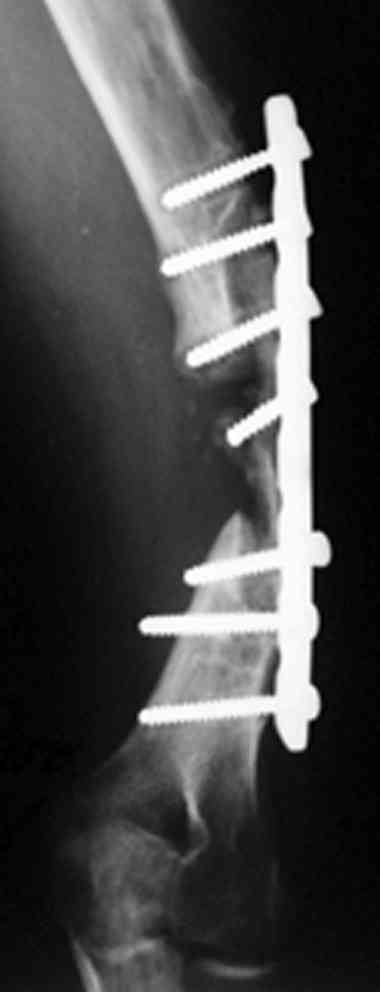

В подобном случае мы бы применили чрескостный остеосинтез. Пример - в приложении.